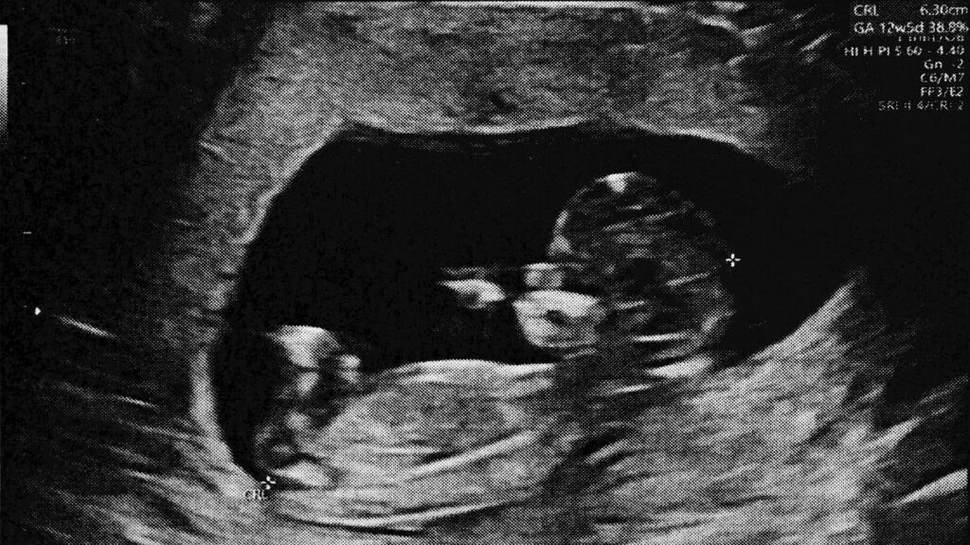

La 13 zile după transfer, femeia a avut primul test de sarcină pozitiv, care a progresat până la o sarcină clinică confirmată. La 8 săptămâni de gestație, pacienta a trecut la îngrijire obstetrică, ecografia arătând o dezvoltare fetală normală și o frecvență cardiacă de 172 bătăi pe minut.